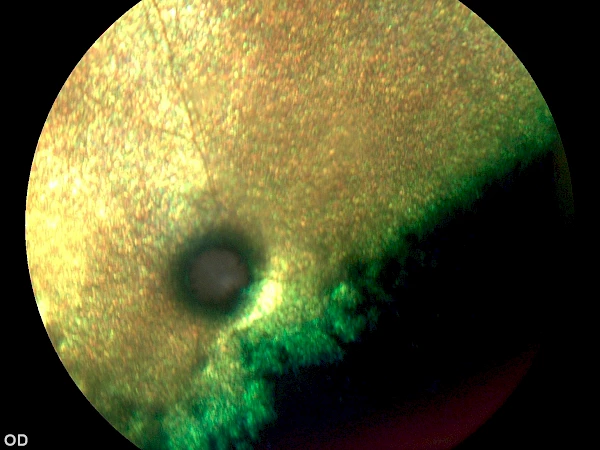

Limbales Melanom vor Operation Limbales Melanom vor Operation

nach Operation nach Operation